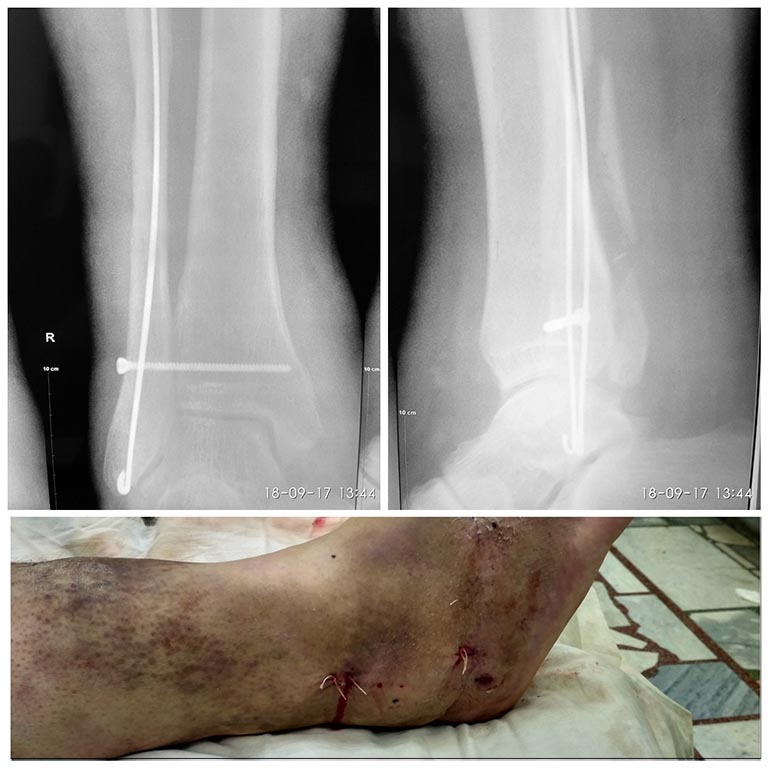

[Ortho] Осложненный перелом лодыжек - подскажите тактику

Критика приветствуется.